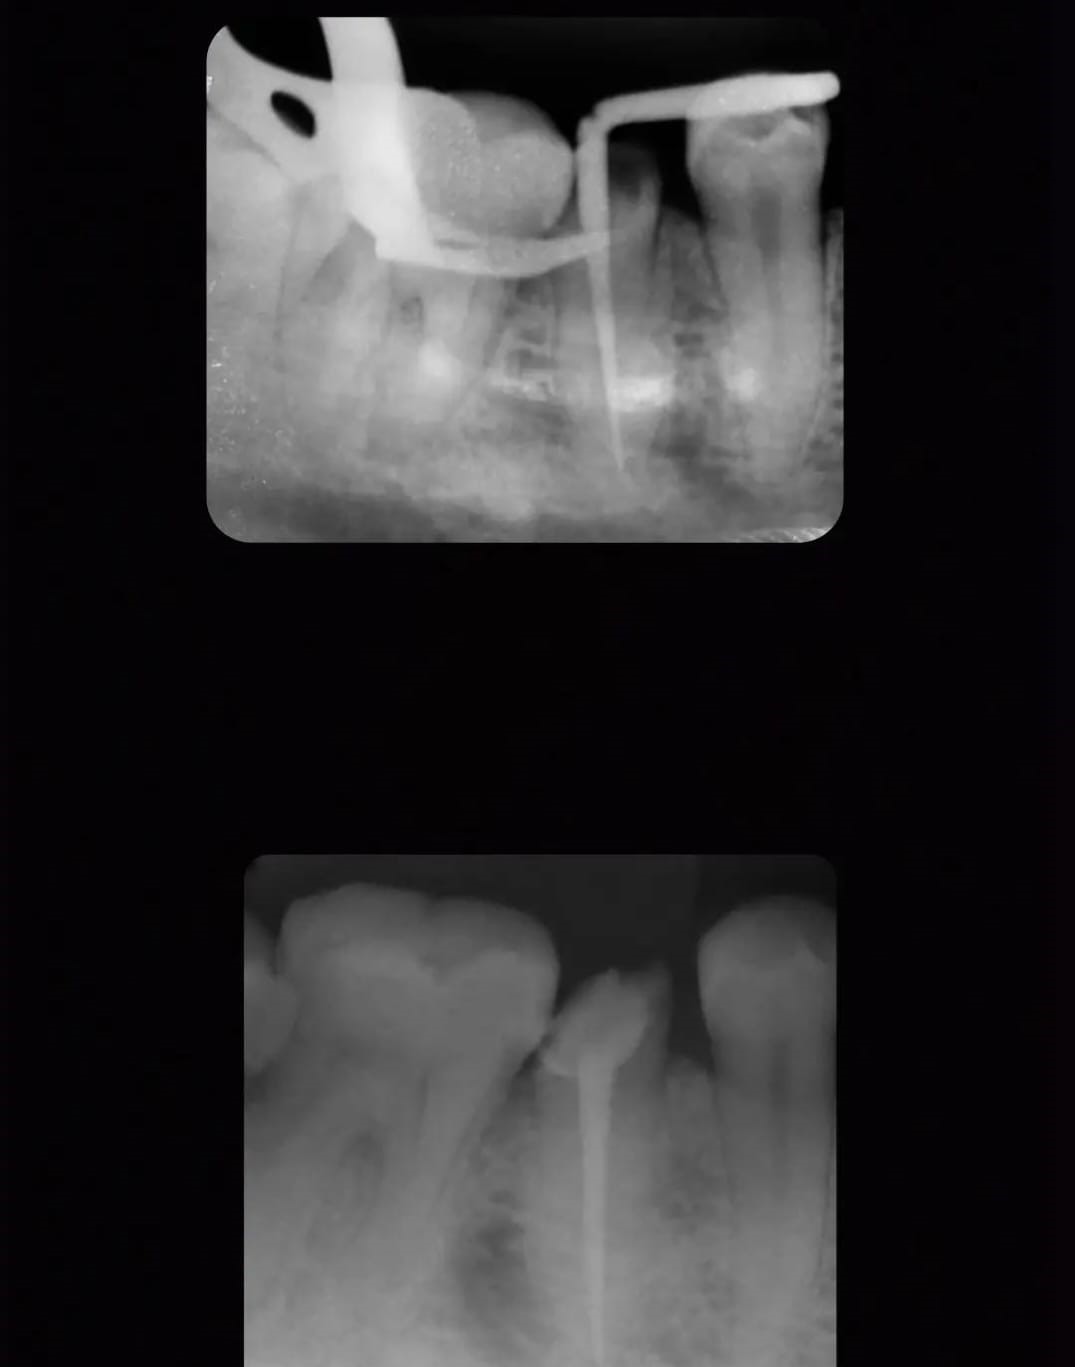

Post 1

Post 2

Post 3

Post 4

Post 5

Post 6